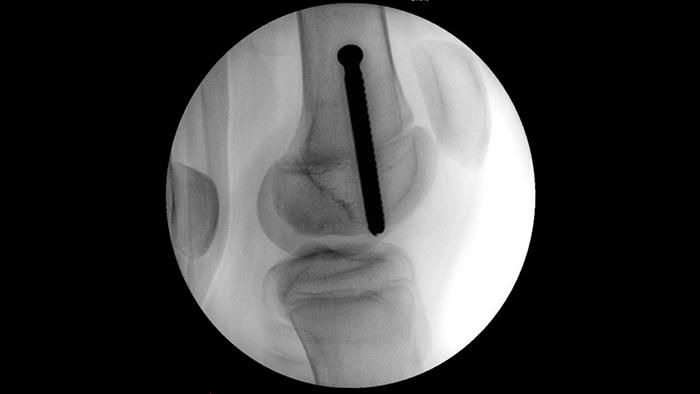

MetalSmart automatically excludes metal artifacts, caused by metal implants, to provide higher image quality and efficient dose control during orthopedic procedures and patients with metal implants, compared to systems without metal exclusion. BodySmart promotes first-time-right imaging and dose efficiency by automatically adapting the measuring field to the area of interest.